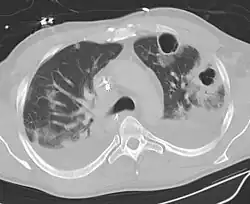

Lung abscesses are often on one side and single involving posterior segments of the upper lobes and the apical segments of the lower lobes as these areas are gravity dependent when lying down. Presence of air-fluid levels implies rupture into the bronchial tree or rarely growth of gas forming organism.

Pulmonary abscess on CT scan